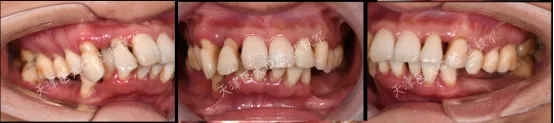

口内检查

· 下颌多颗后牙缺失 ,上下前牙成扇形排列,余留牙除上中切牙 1度松动外,其余牙均2-3度松动。

· 面部对称、三等分,面中线与中切牙中线不一致,高位笑线,上下唇无法自然闭合。

· 上唇丰满度:过度,鼻唇角80 °(鼻唇角正常范围:90 °-105 °),上下唇超出美学E线,凸面型;

· 颞下颌关节:无肌肉压痛,张口偏斜等阳性体征。